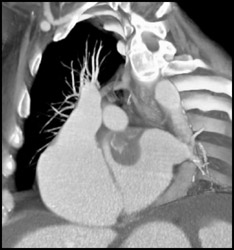

Cavernous Transformation of the Portal Vein (CTPV)